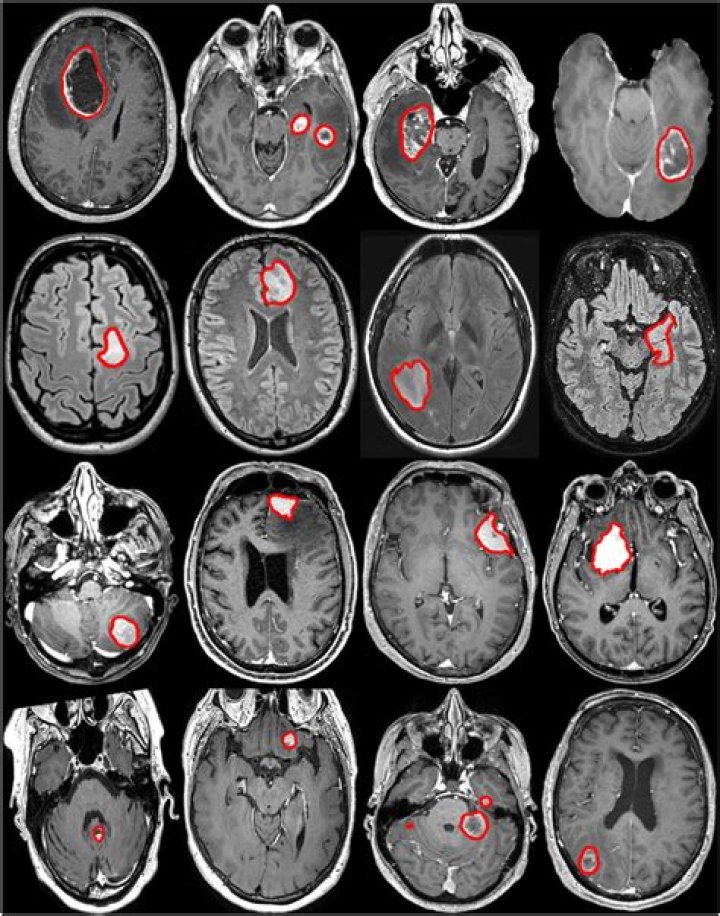

It is almost impossible to diagnose a brain tumor based upon headaches alone. Typically, another symptom, like vision changes, is the trigger for a person to see a physician and to result in the necessary diagnostic testing. An MRI is often the first diagnostic tool to determine if a brain tumor is present.